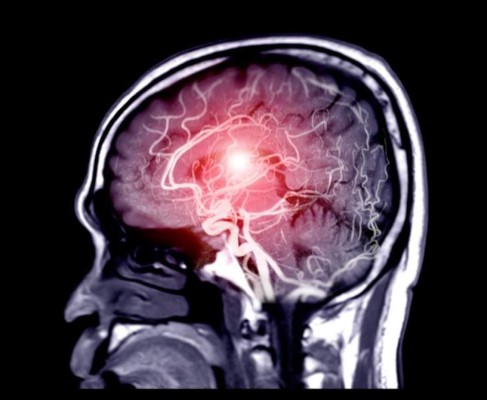

Estudios de 2020 y 2021 revelan que cuando el virus ataca el sistema nervioso central tiene la capacidad de adherirse a las células nerviosas y a las neuronas, ocasionando lo que se conoce como isquemia cerebral o hemorragias cerebrales, detalló al participar en el Club de Neurociencias, de la Facultad de Psicología de la UNAM.

El especialista expuso que otro trabajo, efectuado por Mukesh Kumar, de la Universidad del estado de Georgia, y publicado recientemente en la revista Virology, revisó la presencia de infartos cerebrales mediante resonancia magnética y tomografía computarizada, donde se aprecian manchas negras en el cerebro de los pacientes, inclusive en cortes cerebrales de quienes fallecieron se muestran los infartos cerebrales hemorrágicos.

"Como ya se ha dicho desde hace tiempo, los infartos cerebrales tienen dos causas principales: la primera es una hemorragia por la ruptura de vasos sanguíneos (infarto hemorrágico); y la otra es por la falta de oxígeno, un proceso que se le llama anoxia, debido a la obstrucción por un coágulo (infarto isquémico)", precisó.

Los resultados de Kumar fueron reforzados por un estudio del Departamento de Neurología y Patología del Hospital General de Massachusetts y la Escuela de Medicina de Harvard, donde hicieron cortes al cerebro de fallecidos por el COVID-19, encontrándose nódulos calcificados, evidencias de hemorragias y neuronas hipóxicas.